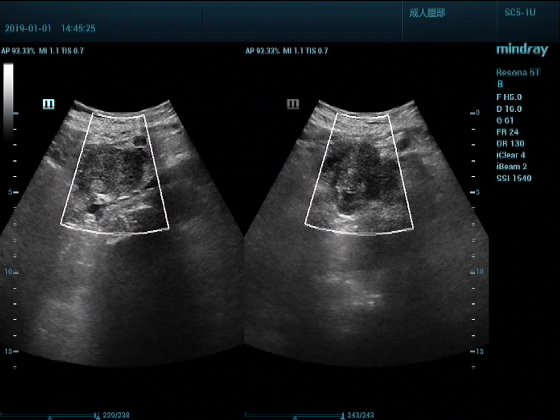

超声入门贴959--胰头癌并胰管扩张

男,88岁,腹部隐疼2个月加重3天来诊